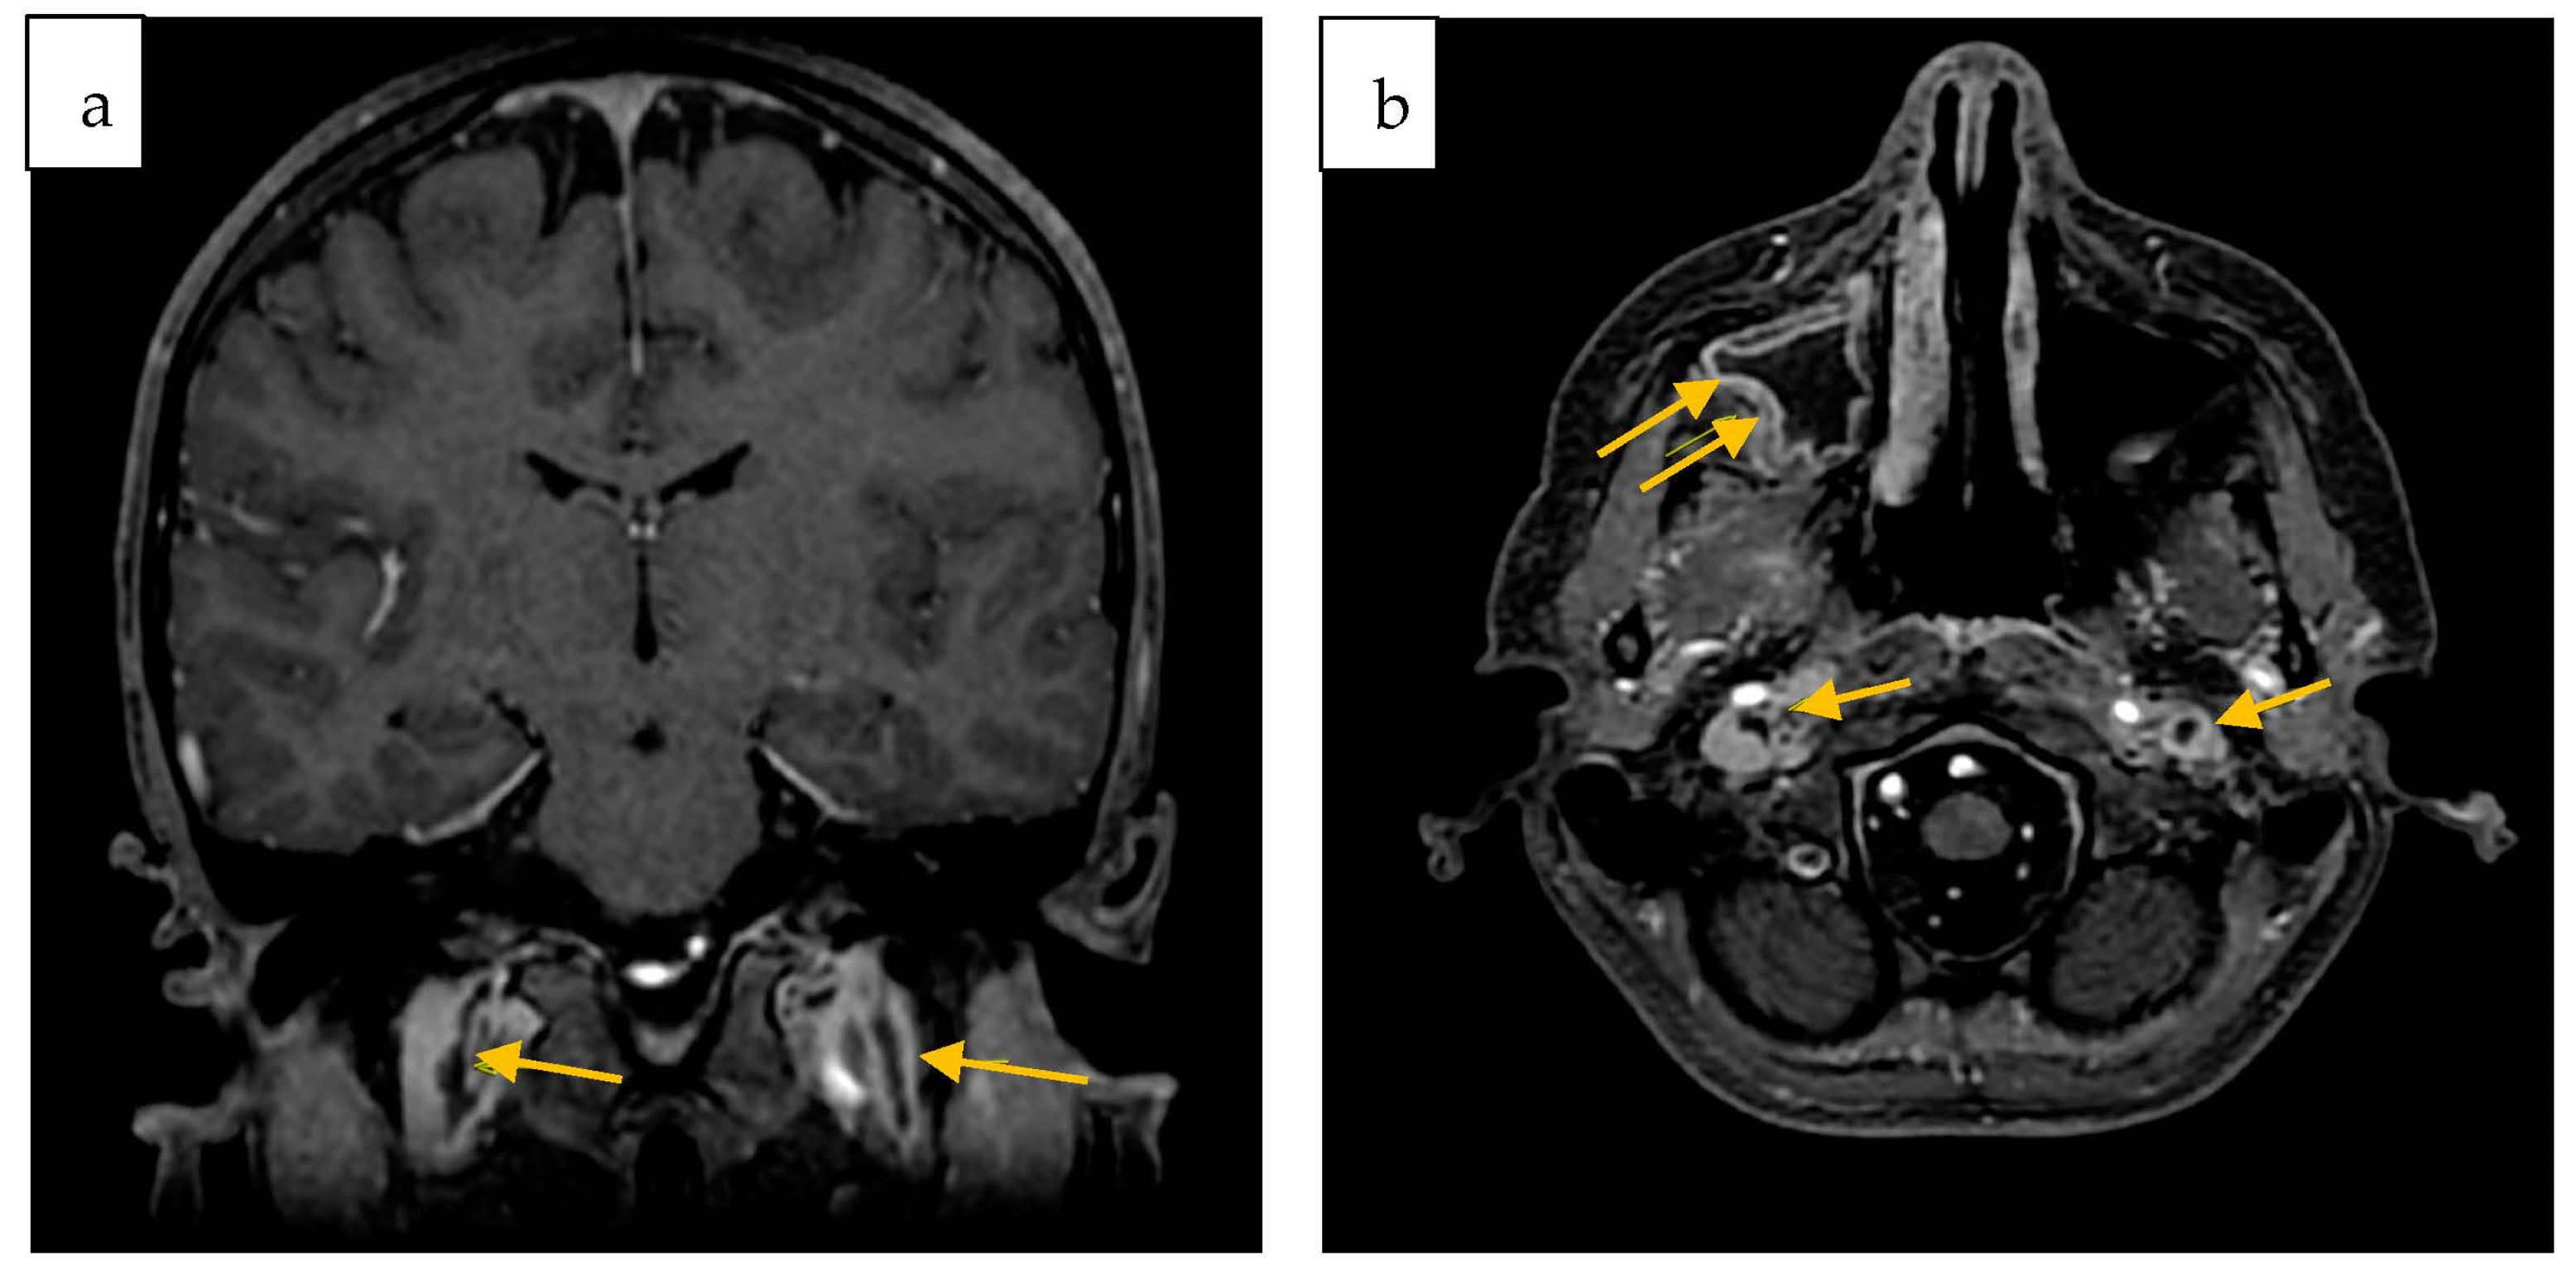

2. Case Report

| Colomba C. et al./Italy/2023 | 12 y | M | No | No | sinus drainage material | sinusitis, meningitis, CSVT | ceftriaxone + vancomycin + metronidazole → cefotaxime | healed |